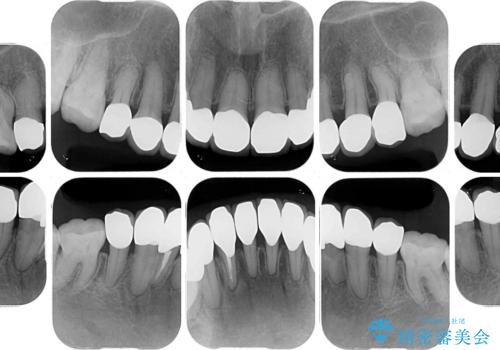

- 小さいころからの歯の変色と矯正治療の後戻りを気にして来院された患者様です。

気になる変色歯を仮歯に変え、その後歯列不正を矯正治療で改善し、最後にオールセラミッククラウンにて補綴治療することとしました。